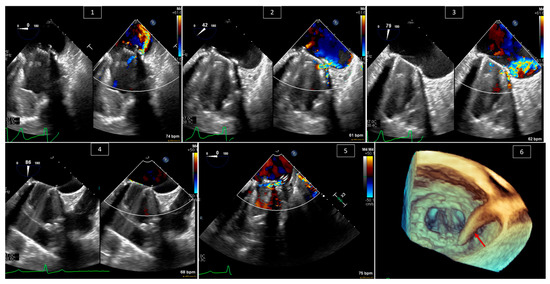

4. Transcatheter Edge-to-Edge Repair (TEER) of Systemic AV Valve